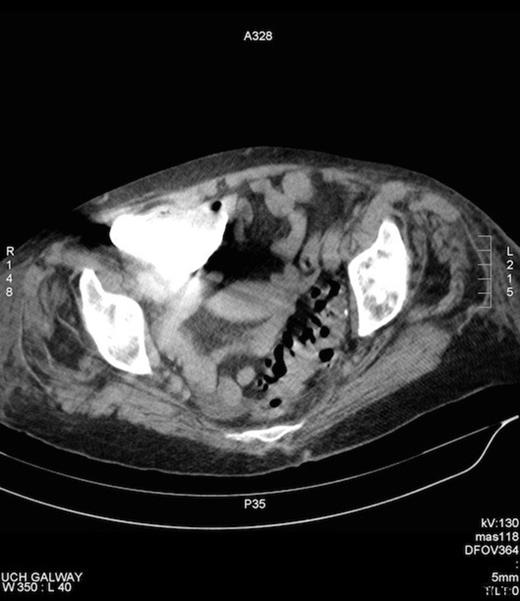

Amyand’s hernia is difficult to diagnose clinically and is rarely diagnosed preoperatively. In a review of 60 cases over a 12 year period only one case was diagnosed pre operatively (7). The difficulty in diagnosis has its origins in the considerable variation of symptoms that patients present with, depending on if the appendix is normal, incarcerated or perforated with the commonest presenting symptom being painful inguinal or inguinoscrotal swelling while the history and examination usually point to an incarcerated hernia (8). Fever and leukocytosis are inconsistent findings. Preoperative CT has revealed the previously unsuspected diagnosis in an occasional report and is useful in establishing the diagnosis early but is not routinely used in clinical situations where a complicated hernia is suspected. Laermann et al illustrated that combining CT with Multi Planar Reconstruction is the most useful technique, to better visualise the appendix and its relationship with surrounding structures, thus aiding in confidently making the correct diagnosis pre-operatively (6). In our case, the appendix could not be visualised, given that the patient has bilateral hip prosthesis, which produced artefact at the level of the appendix. (Figure 4.)

Artefact on CT, secondary to bilateral hip prosthesis, which obscures the appendix.